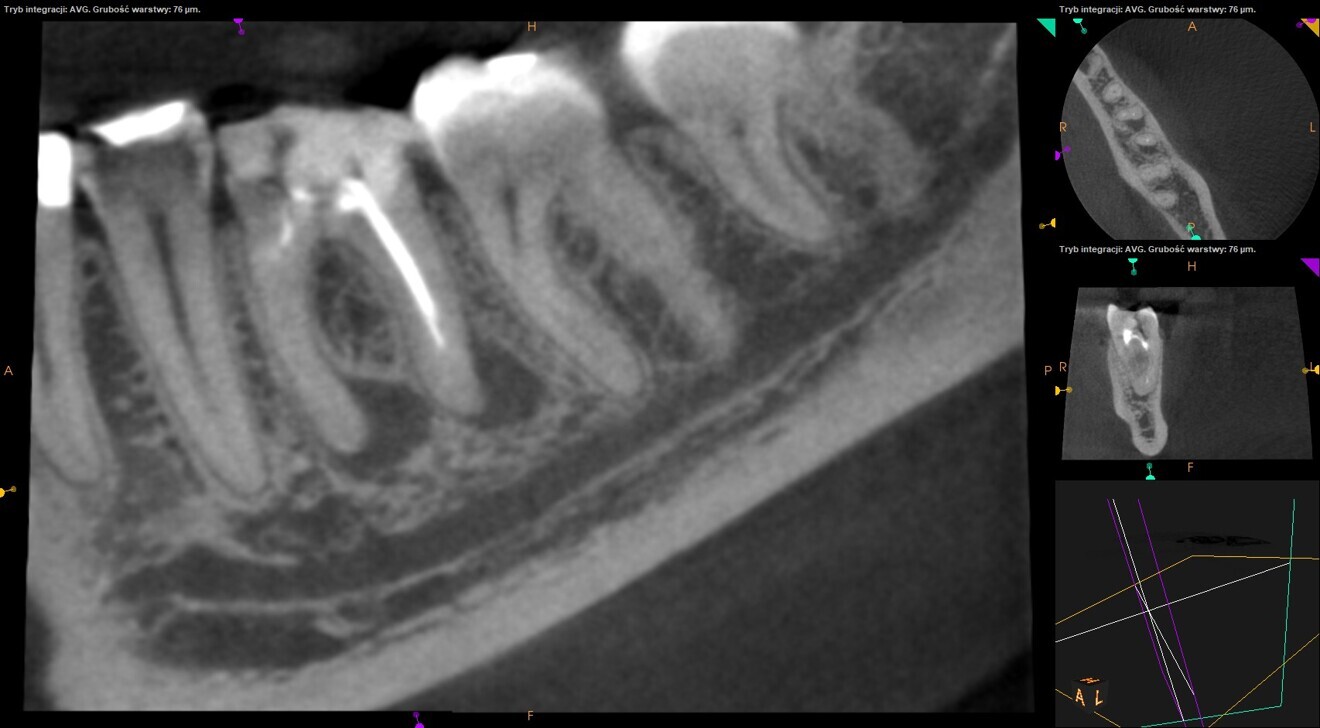

Fig. 2: Pre-op CBCT scan. Broken file far beyond the canal curvature.

Fig. 3: Pre-op CBCT scan. Tip of the broken file located below the junction of the mesiobuccal and mesiolingual canals.

The periapical radiograph and the CBCT scan revealed that the file had broken far beyond the curvature in the mesiobuccal canal and below the junction with the mesiolingual canal. Also, a periapical lesion was visible around the apices of the mesial and distal roots (Figs. 1–3). The length of the file was approximately 5 mm. Bypassing the file through the mesiolingual canal would have been a risky procedure because it may have caused the fracture of the second instrument and the obturation may also have been very challenging. Thanks to SWEEPS technology and a bioceramic sealer, an alternative approach could be taken. After administering anaesthesia and placing a dental dam, the temporary restoration was removed (Figs. 4 & 5). The pulp chamber was rinsed with 5.25% sodium hypochlorite and the irrigant activated with ultrasonics. After cleaning the chamber of the tooth, the dental dam and clamp were rinsed with water and dried and flowable dental dam was placed to seal the tooth and enlarge the space in the pulp chamber for the laser-activated irrigation (Fig. 6). Activation was performed with the SkyPulse laser (Fotona). The AutoSWEEPS mode was chosen. The power of activation was set to 1 W. The flat SWEEPS 300/20 fibre tip was used (Fig. 7). The tip was placed slightly below the orifice of the mesiobuccal canal for the majority of the irrigation with sodium hypochlorite. After 120 seconds of activation with sodium hypochlorite, the tip was placed in the pulp chamber to activate the sodium hypochlorite in all the canals simultaneously for 30 seconds. This procedure was continued for 30 minutes. Only the distal canal was shaped with rotary files, up to size 40/.04. Both mesial canals remained the same size as they were before the file broke during the primary treatment. Finally, the canals were flushed with EDTA activated with AutoSWEEPS at a power of 0.4 W, and sodium hypochlorite was activated for three cycles with AutoSWEEPS at a power of 0.6 W and with a 30-second break for the resting phase. The irrigant flow between the mesiobuccal and mesiolingual canals was rapid, indicating that obturation could be performed.